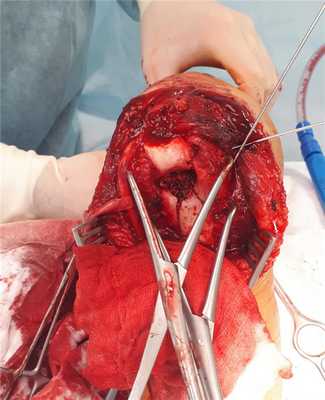

Для адекватной визуализации чаще всего используется доступ с остеотомией локтевого отростка, так как он обеспечивает максимально хорошую визуализацию как мыщелков плеча так и всего блока плечевой кости. При этом доступе производится шевронная остеотомия локтевого отростка, который после выполнения остеосинтеза мыщелков плеча фиксируется спицами и проволочной петлёй по Веберу.

После выполнения остеотомии и бережной сепарации сухожилия трицепса, необходимо выделить локтевой нерв и взять его на держалку, для профилактики его повреждения при выполнении остеосинтеза.

После мобилизации всех отломков становится понятно произошло ли смятие кости, и есть ли возможность адекватного восстановления суставной поврехности, при наличии значительного дефекта кости может потребоваться костная пластика, в случае если этот дефект включает в себя большую часть блока плечевой кости как альтернативный вариант может расматриваться первичное эндопротезирование локтевого сустава.

Мыщелки плеча представляют собой треугольник, стороны которого образованы двумя колоннами и суставной поверхностью, с отверстием для локтевого отростка в центре. При остеосинтезе перелома мыщелков плеча необходимо восстановить все 3 стороны этого треугольника.

В первую очередь восстанавливается суставная поверхность. При отсутсвии сминания кости, или утерянных фрагментов, блок и головчатое возвышение могут быть соединены 2 компрессирующими винтами. Сначала фрагменты временно фиксируются спицами киршнера и костными цапками, так называемая прелиминарная фиксация.

После достижения удовлетворительной репозиции через блок параллельно его длинной оси проводится 1-2 компрессирующих винта.

Следующим этапом уже «собранный» блок фиксируется к медиальной и латеральной колоннам спицами, а потом уже вся эта конструкция при помощи пластин фиксируется к диафизу плечевой кости.